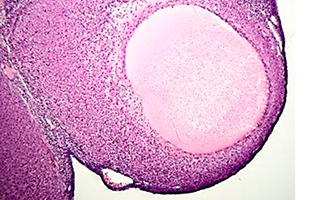

Las doctoras Myriam Laconi y Laura Pelegrina, la veterinaria Cáceres y las biólogas Asensio y Sahuenza (investigadoras y docentes del Conicet, la Universidad Juan Agustín Maza y la Universidad de Mendoza) explican a Argentina Investiga que en los modelos experimentales con los que trabajan, la Allopregnanolona –a dosis farmacológicas– provoca una inhibición en la ovulación de las ratas tratadas, de modo que quizás pueda pensarse en esta hormona como una nueva droga anovulatoria con muy escasos efectos colaterales.

Debido a la relevancia del cáncer de ovario la doctora Laconi explica que en su laboratorio se están haciendo experimentos en líneas celulares tumorales humanas para descubrir el potencial de Allopregnanolona en el cáncer de ovario, midiendo los niveles de proliferación celular, apoptosis y la generación de nuevos vasos sanguíneos, aspectos de gran importancia en los procesos tumorales.